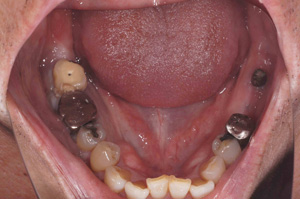

@‚j.‚l.‚³‚ñ @‚T‚OÎ@’j«@ ‰ïŽÐ–ðˆõ @Žèp“ú  ‚Q‚O‚P‚U”N  ‚P‚PŒŽ ‚Q‚T“úi‹àj@㉺Š{ ƒm[ƒxƒ‹ƒKƒCƒhŽg—p{‚b‚f‚e•¹—p with Sinus Lift@Ö¬“à’¾Ã•¹—p

@@@@@@@@@ãŠ{@‚X–{ @@‘¦Žž‘•’…iƒvƒƒr‘•’…j

@@@@@@@@@‰ºŠ{  ‚W–{@ @’x‰„‰×diƒq[ƒŠƒ“ƒOƒLƒƒƒbƒv‘•’…j